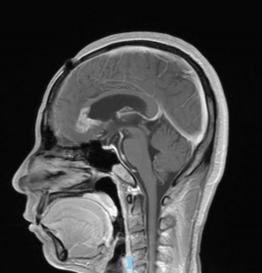

44歲的郭先生(化姓)為膠質(zhì)瘤復(fù)發(fā)患者,復(fù)查發(fā)現(xiàn)顱內(nèi)占位進(jìn)行性進(jìn)展1周,MRI檢查提示瘤體已累積到胼胝體,且瘤體位置較深,手術(shù)難度極高。面對這一挑戰(zhàn),王虎教授團(tuán)隊(duì)決定采用多種先進(jìn)技術(shù)輔助手術(shù),其中最為引人注目的就是首次引入的細(xì)胞級顯微鏡EndoSCell?。該設(shè)備是目前全球唯一實(shí)時(shí)在體細(xì)胞級顯影的儀器,可以輔助醫(yī)生從細(xì)胞層面區(qū)分腫瘤組織與正常組織,從而做到細(xì)胞級精準(zhǔn)切除。

患者術(shù)前核磁影像

整個(gè)手術(shù)過程在“腦醫(yī)匯”平臺進(jìn)行了全程直播,吸引了近千位神經(jīng)外科領(lǐng)域的專家學(xué)者觀看,他們紛紛對王虎教授團(tuán)隊(duì)的精湛技藝和EndoSCell?的先進(jìn)技術(shù)表示贊賞。術(shù)后,患者的生命體征平穩(wěn),CT及MRI檢查顯示腫瘤切除滿意,無明顯出血和并發(fā)癥。患者神志清醒,精神狀態(tài)良好,目前恢復(fù)良好。